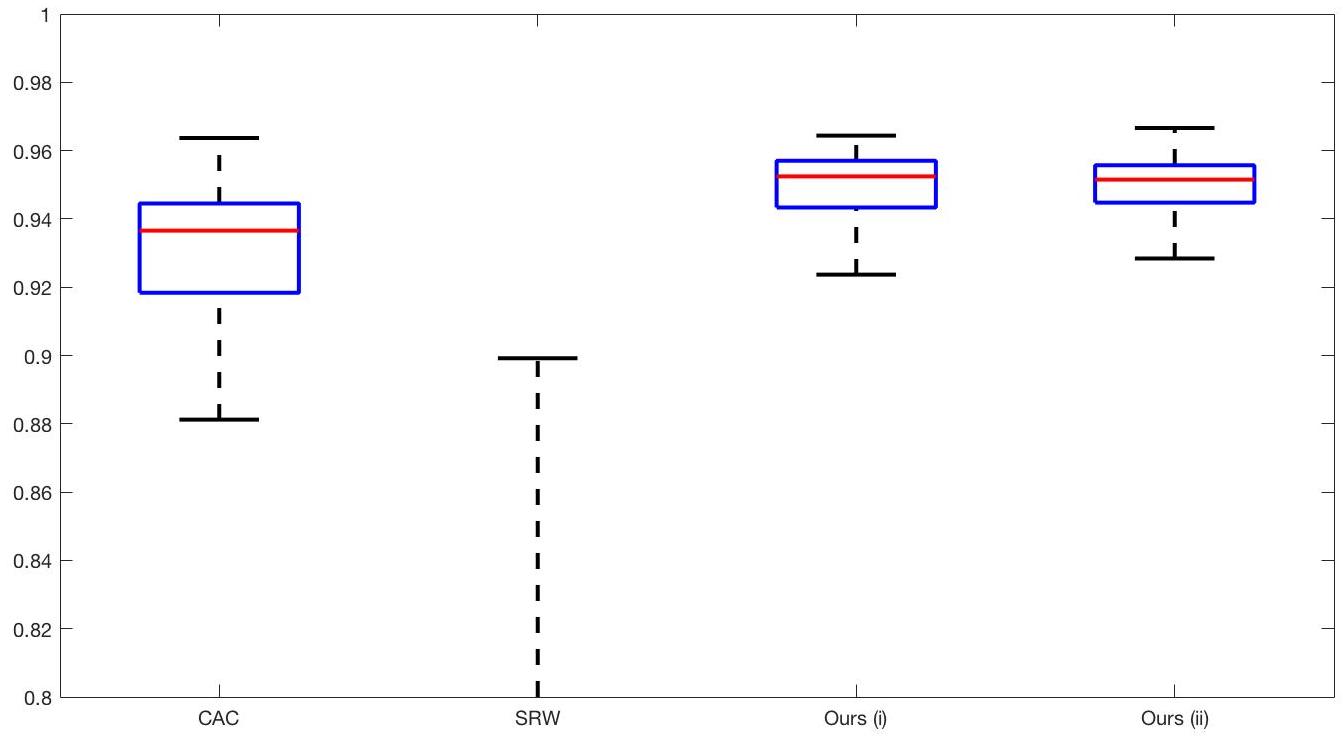

In order to further establish the robustness of our method, we now introduce the results of testing our approach against competing interactive segmentation methods on a larger data set. The results are presented in Fig. 17, showing a boxplot of accuracy in terms of TC on a set of 30 CT images (excluding outliers). The target structure we consider is the spleen, as this consists of a relatively homogeneous foreground, appropriate for the approach considered. The data has been manually contoured providing ground truth data for the image set. We compare CAC Nguyen:12 and SRW SRW against our method with five variations of user input for each image. It is worth emphasising here that the input used in the tests is identical for each approach and was not refined in any way. It was designed to mimic what a user, unfamiliar with each approach, might select intuitively. A representative example for three images is shown in Fig. 18. This shows foreground (red) and background (blue) user input regions. For our method, we define the red region as as discussed in §1 and enforce hard constraints on the blue region. We refer to the results of the proposed approach using this input as Ours (i). We also include results of randomising the user input in an identical way to §7.3. For each image we generate 1000 simulated user input choices, which we present as Ours (ii). It is important to note that the difference between Ours (i) and (ii) is only the definition of . The method and parameters are fixed between each.

The performance of CAC Nguyen:12 is very good, as shown in Fig. 17. We have included an additional figure to highlight the difference between CAC and Ours (i) and (ii) more precisely. This is shown in Fig. 19 (this is the same as Fig. 17 with TC restricted to [0.8,1]). Here we can see that the proposed approach has a slightly better median (0.96 compared to 0.94) and is generally more consistent than CAC. This is particularly evident when considering the worst TC results of CAC () against ours ().

In Fig. 17 it can be seen that our method exceeds the performance of SRW by a large margin (0.66 compared to 0.95). One possible reason for this is that the input used, as displayed in Fig. 18, is restricted to be as intuitive as possible. SRW is capable of achieving improved results with more elaborate foreground/background input. However, it is generally reliant on a trial and error approach which is not ideal in practice. This highlights an important advantage of our method. It is able to achieve a high standard of results with simple user input. This is reinforced by considering Ours (ii), where the results of 30000 random variations of the user input does not cause a drop off in accuracy compared to the 150 manual user input selections. Again, this can be seen more clearly in Fig. 19. In fact, the results for the proposed approach with the random input are slightly better than with the manual input. This underlines the robustness to user input in the model, which is a vital aspect of selective segmentation.